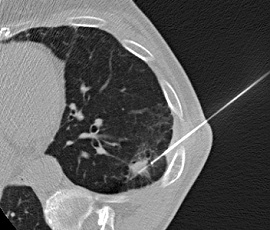

CT画像

CTガイド下針生検